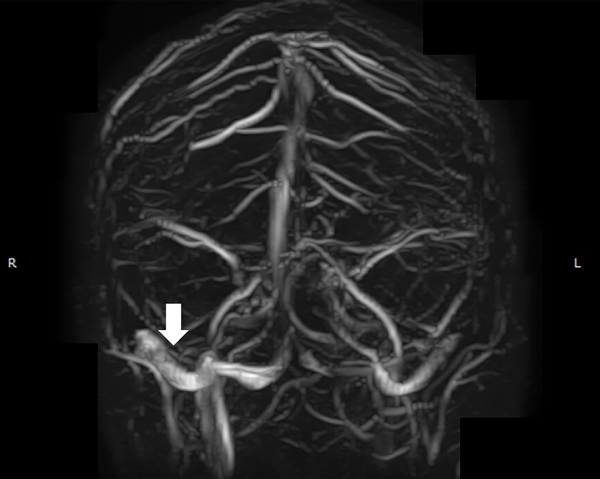

La paciente evolucionó con desaparición de la diplopía inmediatamente después de terminado el procedimiento y con desaparición de la cefalea a los 15 días del mismo sin requerimientos de analgésicos y mejoría de la visión. Se otorgó el alta hospitalaria a las 24 horas del procedimiento continuando con doble antiagregación por 3 meses y dando las pautas de alarma. Se realizó un control con angioRM venosa a los 3 meses evidenciando seno transverso derecho sin estenosis (figura 5).

Figura 5: Angioresonancia en tiempo venoso control a tres meses. La flecha blanca señala el seno transverso derecho sin estenosis.